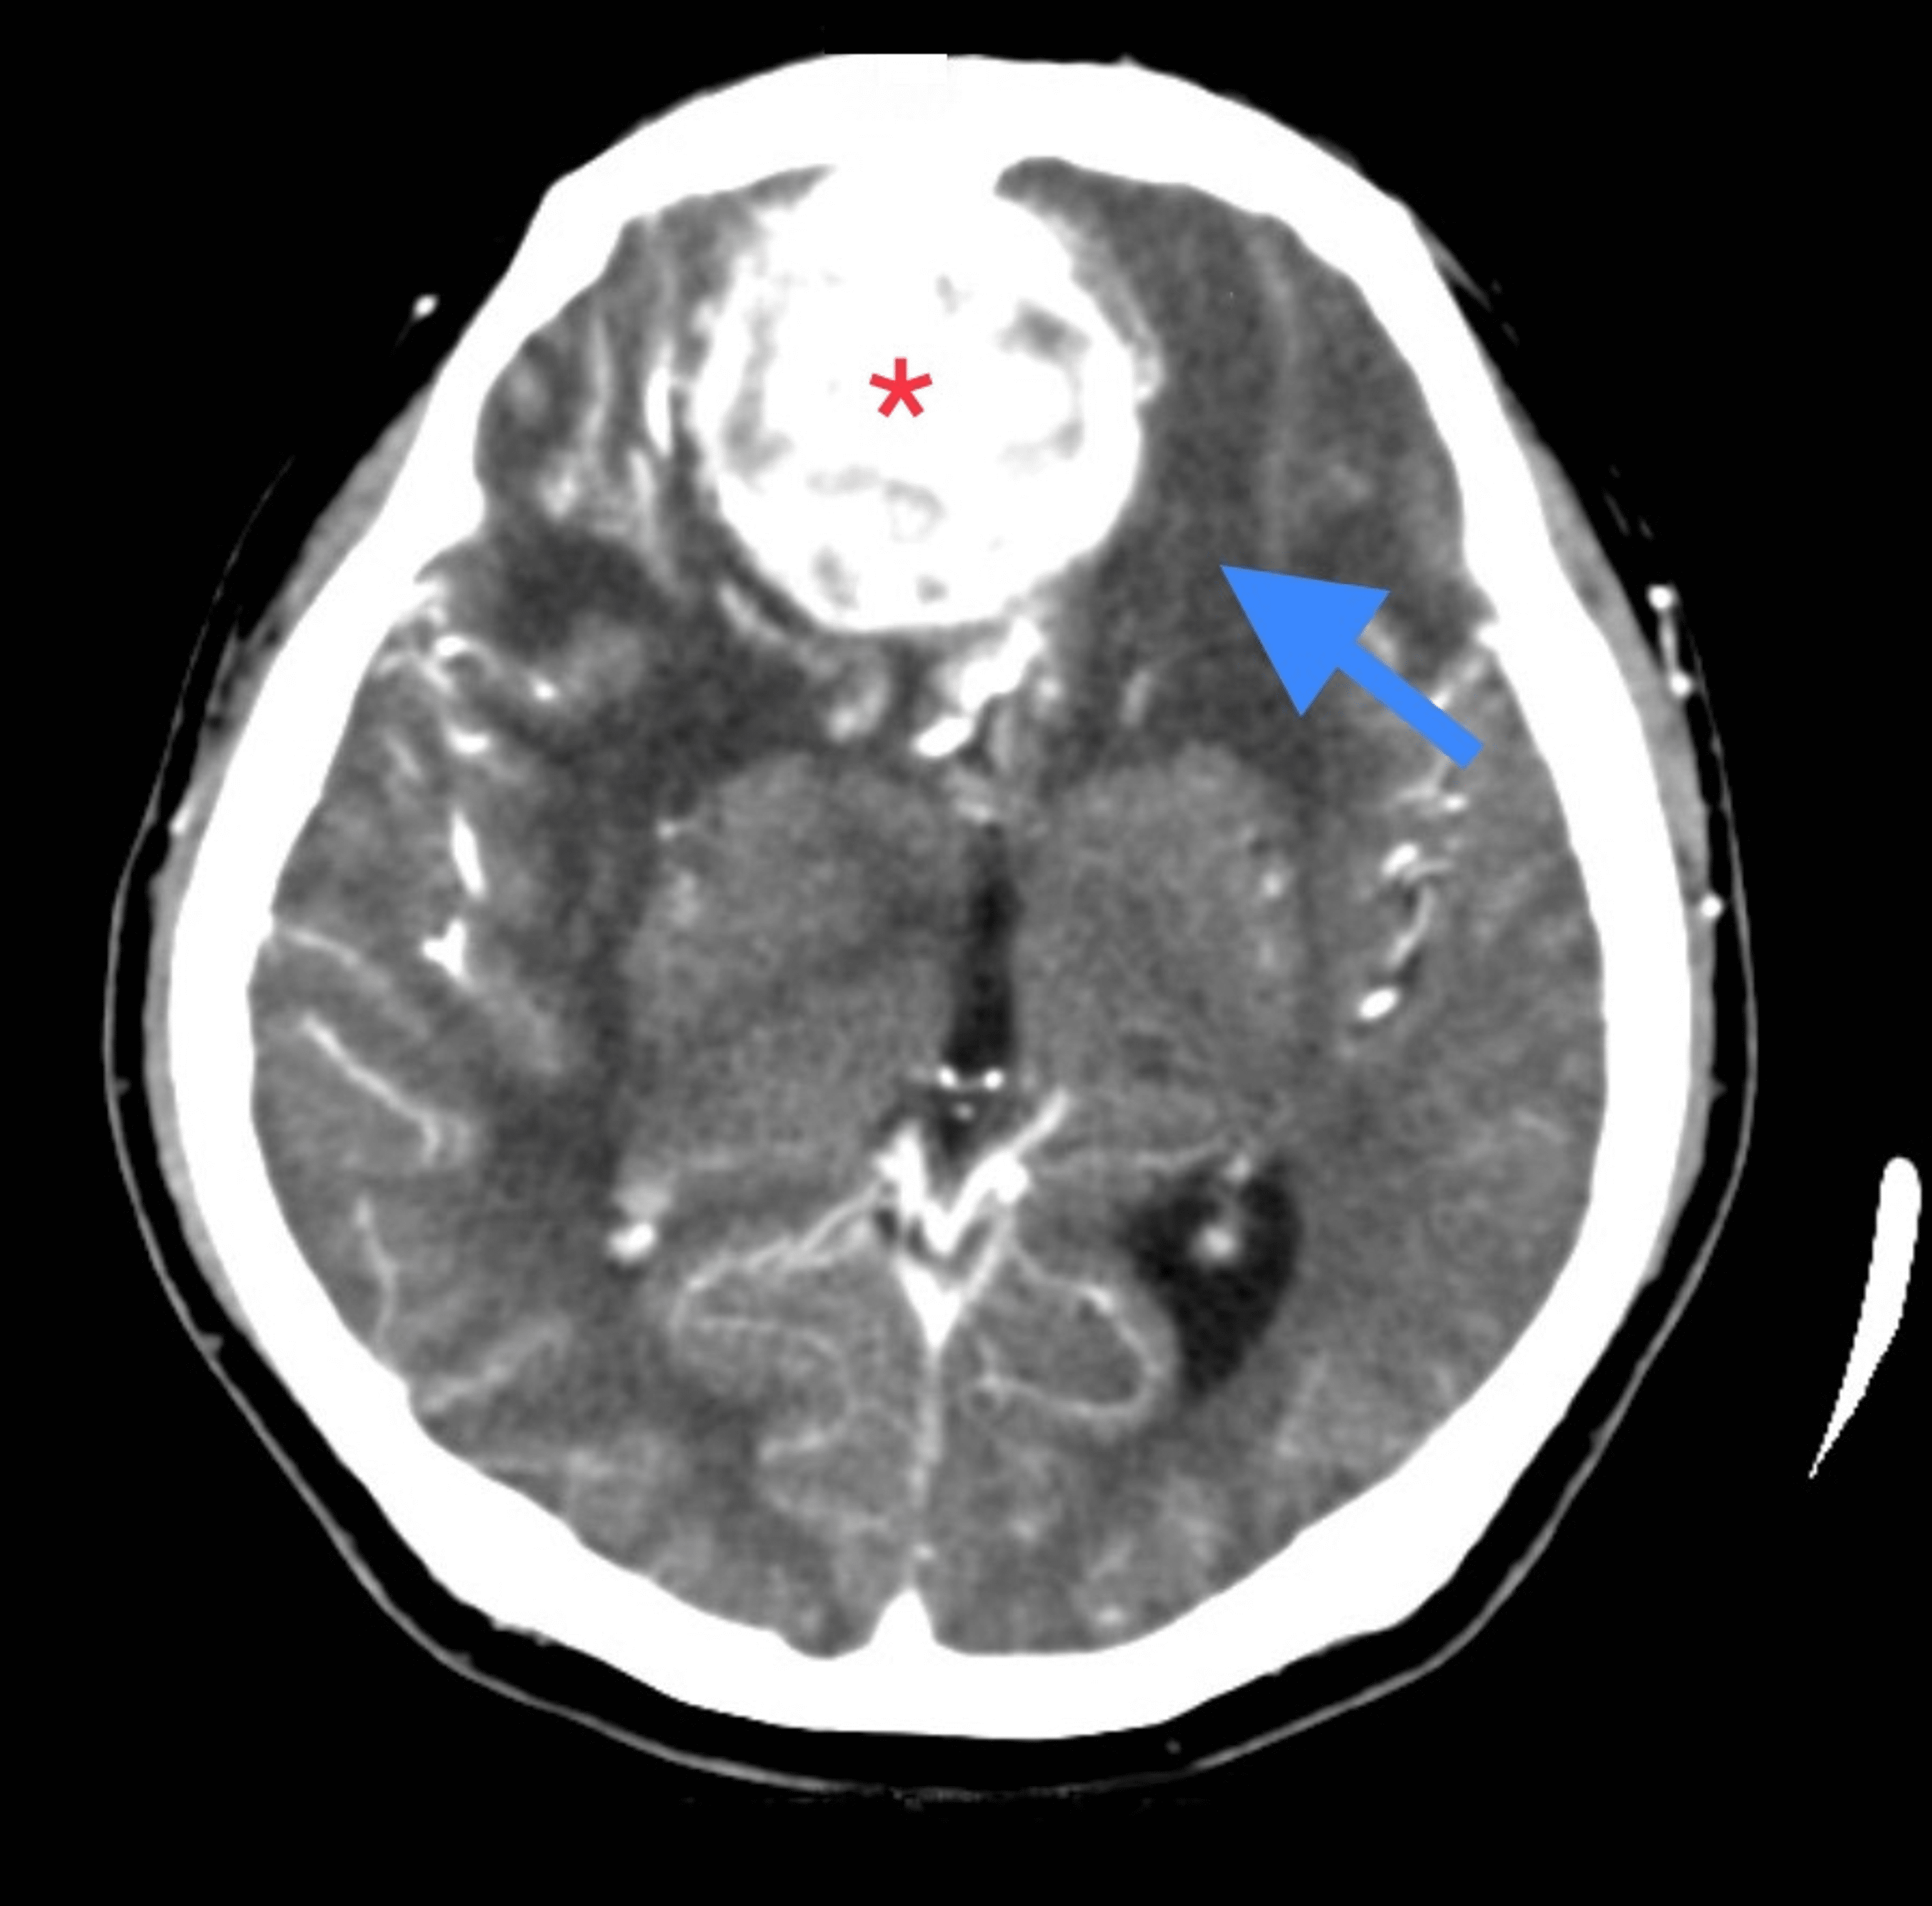

What is olfactory groove meningioma? Olfactory groove meningiomas are located between your brain and nose at the base of your skull. This type of tumor can cause a loss of smell, and can grow large enough to cause problems with vision. They grow near your olfactory nerve,. Olfactory groove meningioma is a specific type of brain tumor that forms along the olfactory groove,. The mount sinai health system specializes in diagnosing and treating olfactory groove meningiomas, which are benign growths that. Olfactory groove meningiomas grow along the nerves that run between the brain and the nose, the nerves allow you to smell. Olfactory groove meningioma forms along the nerves that run between the brain and the nose and account for around 10 percent of meningiomas. Meningioma is a known benign central nervous system tumor commonly arising from the meninges of the brain and spinal cord. Large anterior cranial fossa homogenous space occupying lesion with associated mass effect resulting in.

What Is Olfactory Groove Meningioma What is olfactory groove meningioma? This type of tumor can cause a loss of smell, and can grow large enough to cause problems with vision. The mount sinai health system specializes in diagnosing and treating olfactory groove meningiomas, which are benign growths that. Olfactory groove meningioma is a specific type of brain tumor that forms along the olfactory groove,. Olfactory groove meningiomas grow along the nerves that run between the brain and the nose, the nerves allow you to smell. What is olfactory groove meningioma? Large anterior cranial fossa homogenous space occupying lesion with associated mass effect resulting in. They grow near your olfactory nerve,. The rate of recurrence and the risk of. Meningioma is a known benign central nervous system tumor commonly arising from the meninges of the brain and spinal cord. Olfactory groove meningiomas are located between your brain and nose at the base of your skull. Olfactory groove meningioma forms along the nerves that run between the brain and the nose and account for around 10 percent of meningiomas.

Olfactory groove meningioma (huge) Image What Is Olfactory Groove Meningioma What is olfactory groove meningioma? Large anterior cranial fossa homogenous space occupying lesion with associated mass effect resulting in. This type of tumor can cause a loss of smell, and can grow large enough to cause problems with vision. The mount sinai health system specializes in diagnosing and treating olfactory groove meningiomas, which are benign growths that. The rate of. What Is Olfactory Groove Meningioma.